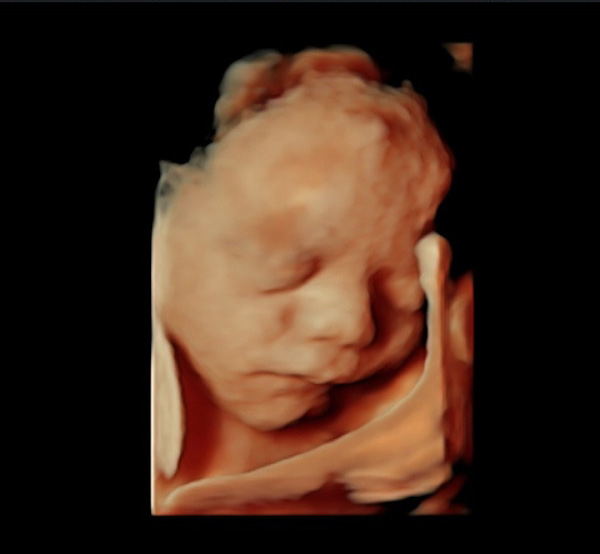

Detaylı ultrason, ikinci düzey ultrason ve ayrıntılı ultrason aynı anlama gelir. Renkli ultrason veya 4 boyutlu ultrason detaylı ultrasonla aynı şey değildir. 4 boyutlu ultrasonda bebeğinizin yüzü veya organlarının güzel bir anı olarak saklanacak fotoğrafı alınır. Detaylı ultrasonda ise bebeğin bütün organları ultrason teknolojisi el verdiğince incelenir

Detaylı ultrasonun yapıldığı cihazın görüntü kalitesi çok iyi olmalıdır. Ayrıca detaylı ultrason için kullanılan cihazın doppler özelliğinin olması gerekir. Yüz gibi bazı kısımlar iki boyutlu ultrasondan ziyade dört boyutlu ultrasonla daha iyi değerlendirilir.

- Bebeklerin genel yüz profilleri, burun kemikleri ve gözlerinde bulunan lenslerin izlemesi yapılır.